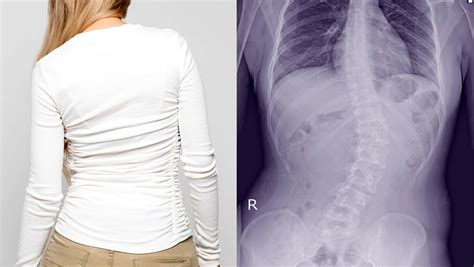

Webthe cornerstone of chiropractic care for scoliosis is spinal realignment. Webchiropractic care in galveston tx is a gentle and conservative approach to treatment that can prevent, slow, and stop the progression of scoliosis. Learn more about the potential side.